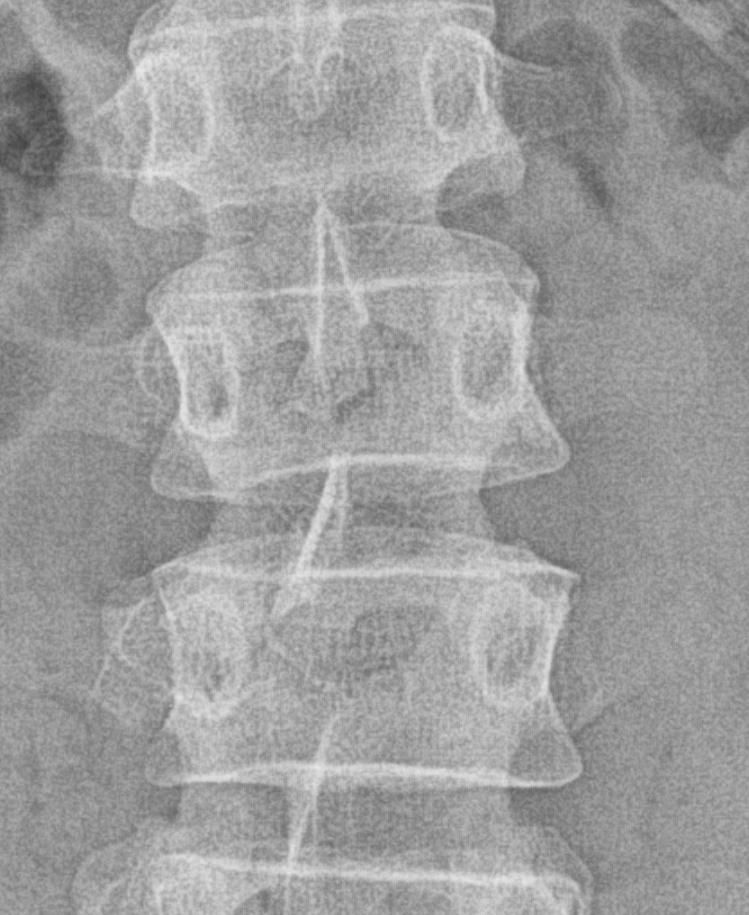

• 1번 째 사진

사진 공유해주신것을 보았을 때 뼈 모양 자체의 문제는 아닐 것으로 생각되며 반복적인 사다리작업으로 인한 근육의 과긴장 및 근육 및 근막의 문제로 인해서 그럴 수 있습니다.

신체 진찰이 필요하겠으나 올려주신 사진으로 미루어 척추 사이 간격은 잘 유지되고 있으나 정상적인 척추의 굴곡이 소실된 상태 입니다.